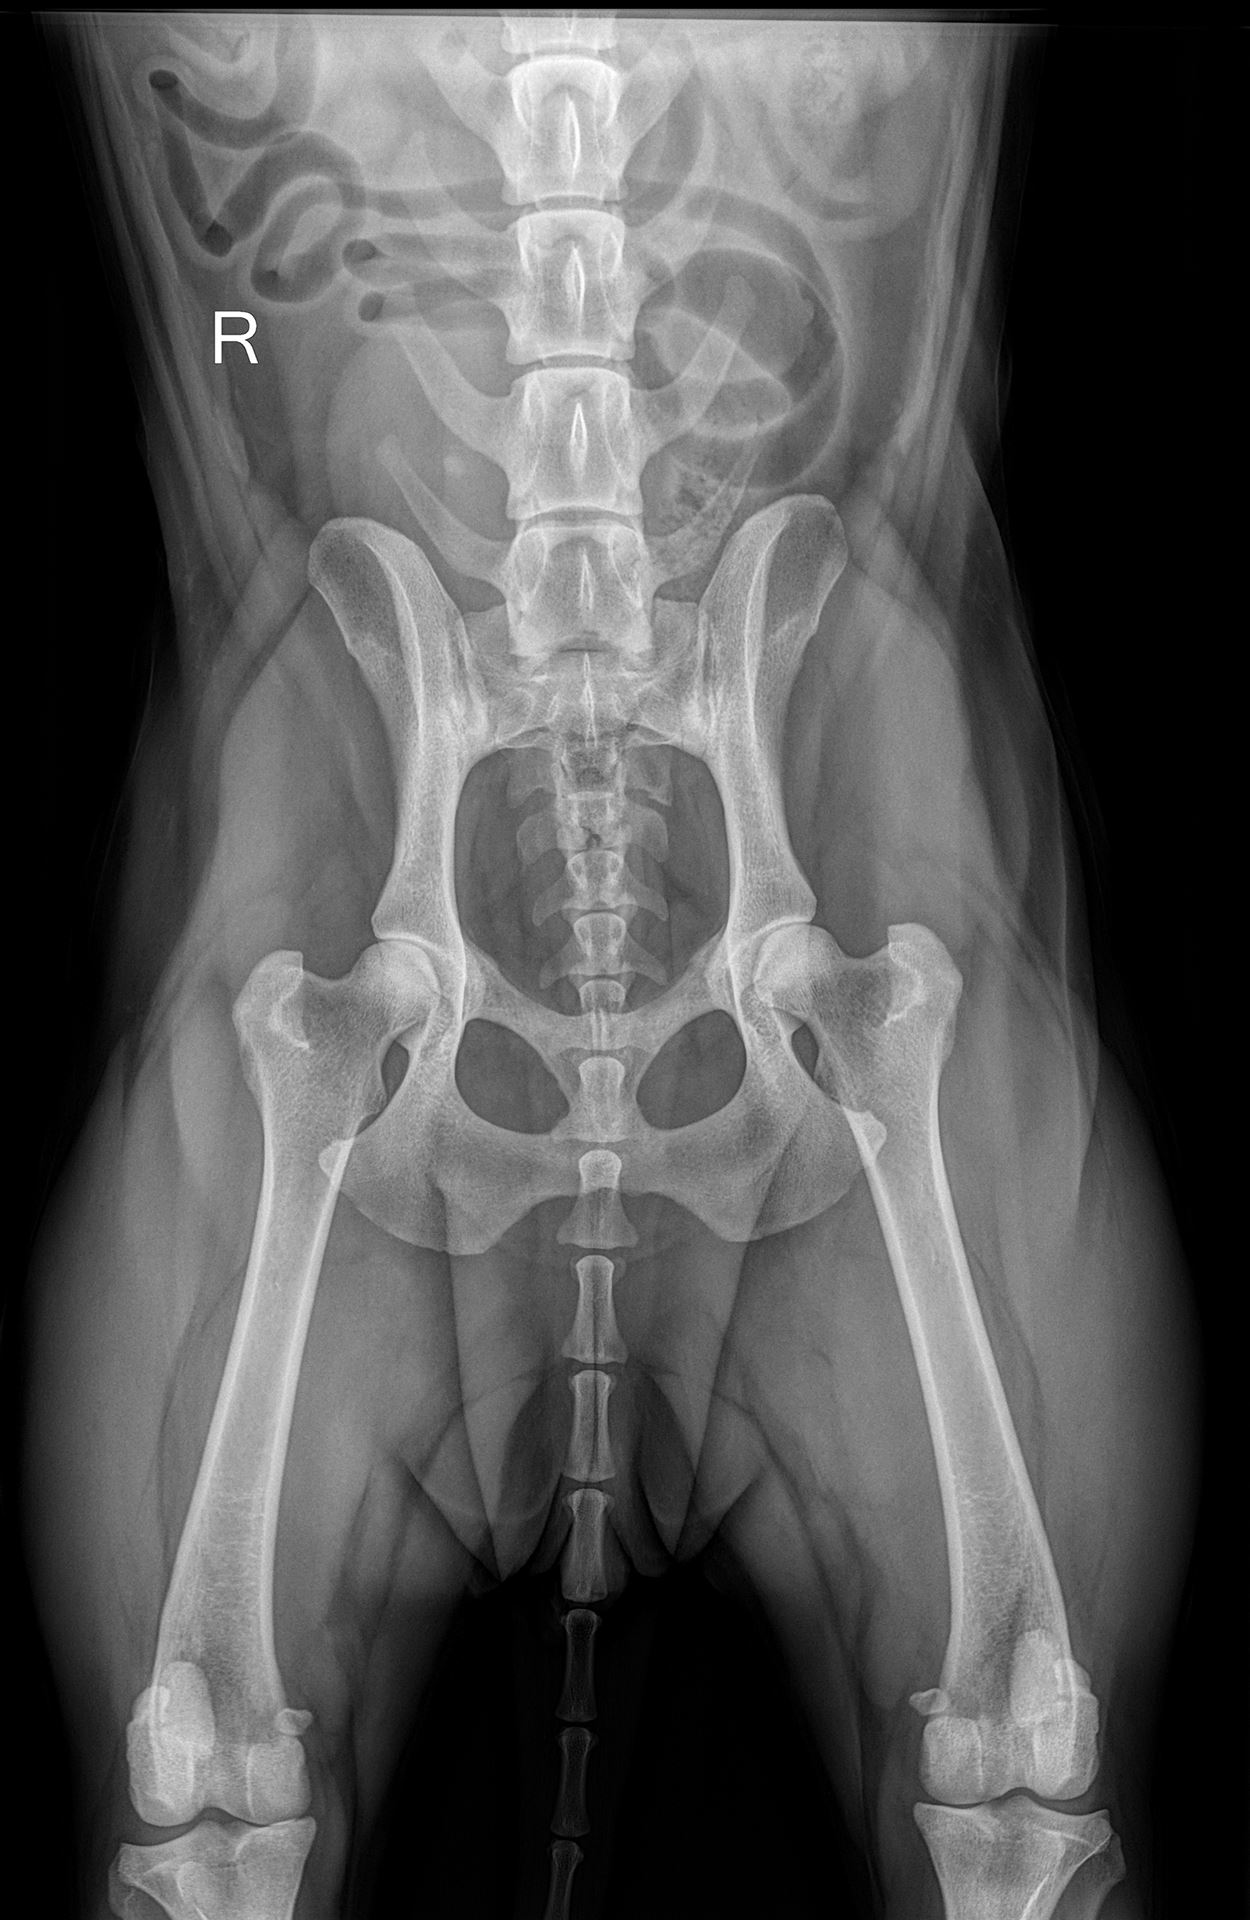

Unsere leistungsfähige Röntgenanlage ermöglicht die Anfertigung qualitativ hochwertiger Aufnahmen von der Katze bis zum Bernhardiner. Röntgenuntersuchungen sind vor allem bei orthopädischen Erkrankungen das Diagnostikum der Wahl, aber auch bei Herz- und Lungenerkrankungen, zur Darstellung von röntgendichten Fremdkörpern und zur Erkennung von Lungentumoren und -metastasen eignet sich die Röntgenuntersuchung hervorragend. Natürlich führen wir auch Zuchttauglichkeitsuntersuchung auf HD, ED und OCD durch.